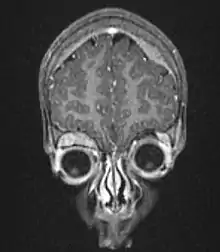

MRI showing orbital and skull vault metastatic NB in 2-year-old